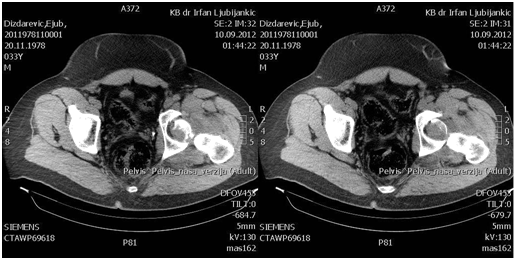

The patient at the age of 34 and 150kg of body weight suffered left hip posterior dislocation with femoral head fracture in car crash accident. The patient had been admitted to hospital after midnight. The mechanism of injury goes as follows: axial force and flexion in the hip caused by impact of the car. The left leg clinically observed is in painful extension, with minimal movement, strong pain and shortened leg. X-rays shows posterior hip joint dislocation and fracture of the femoral head. Closed reduction under anesthesia was unsuccessful. 3D CT reconstruction that had been taken before proceeding to open procedure shows posterior hip dislocation with femoral head fracture above fovea involving weight bearing portion- Pipkin type II fracture dislocation.

Preoperative x-rays, CT scans and 3D CT reconstructions in emergency department are presented as follows (Figure 1-5).

Figure 1 Preoperative X-ray.

Figure 2 Preoperative CT scans.

Figure 3 Preoperative CT scans.